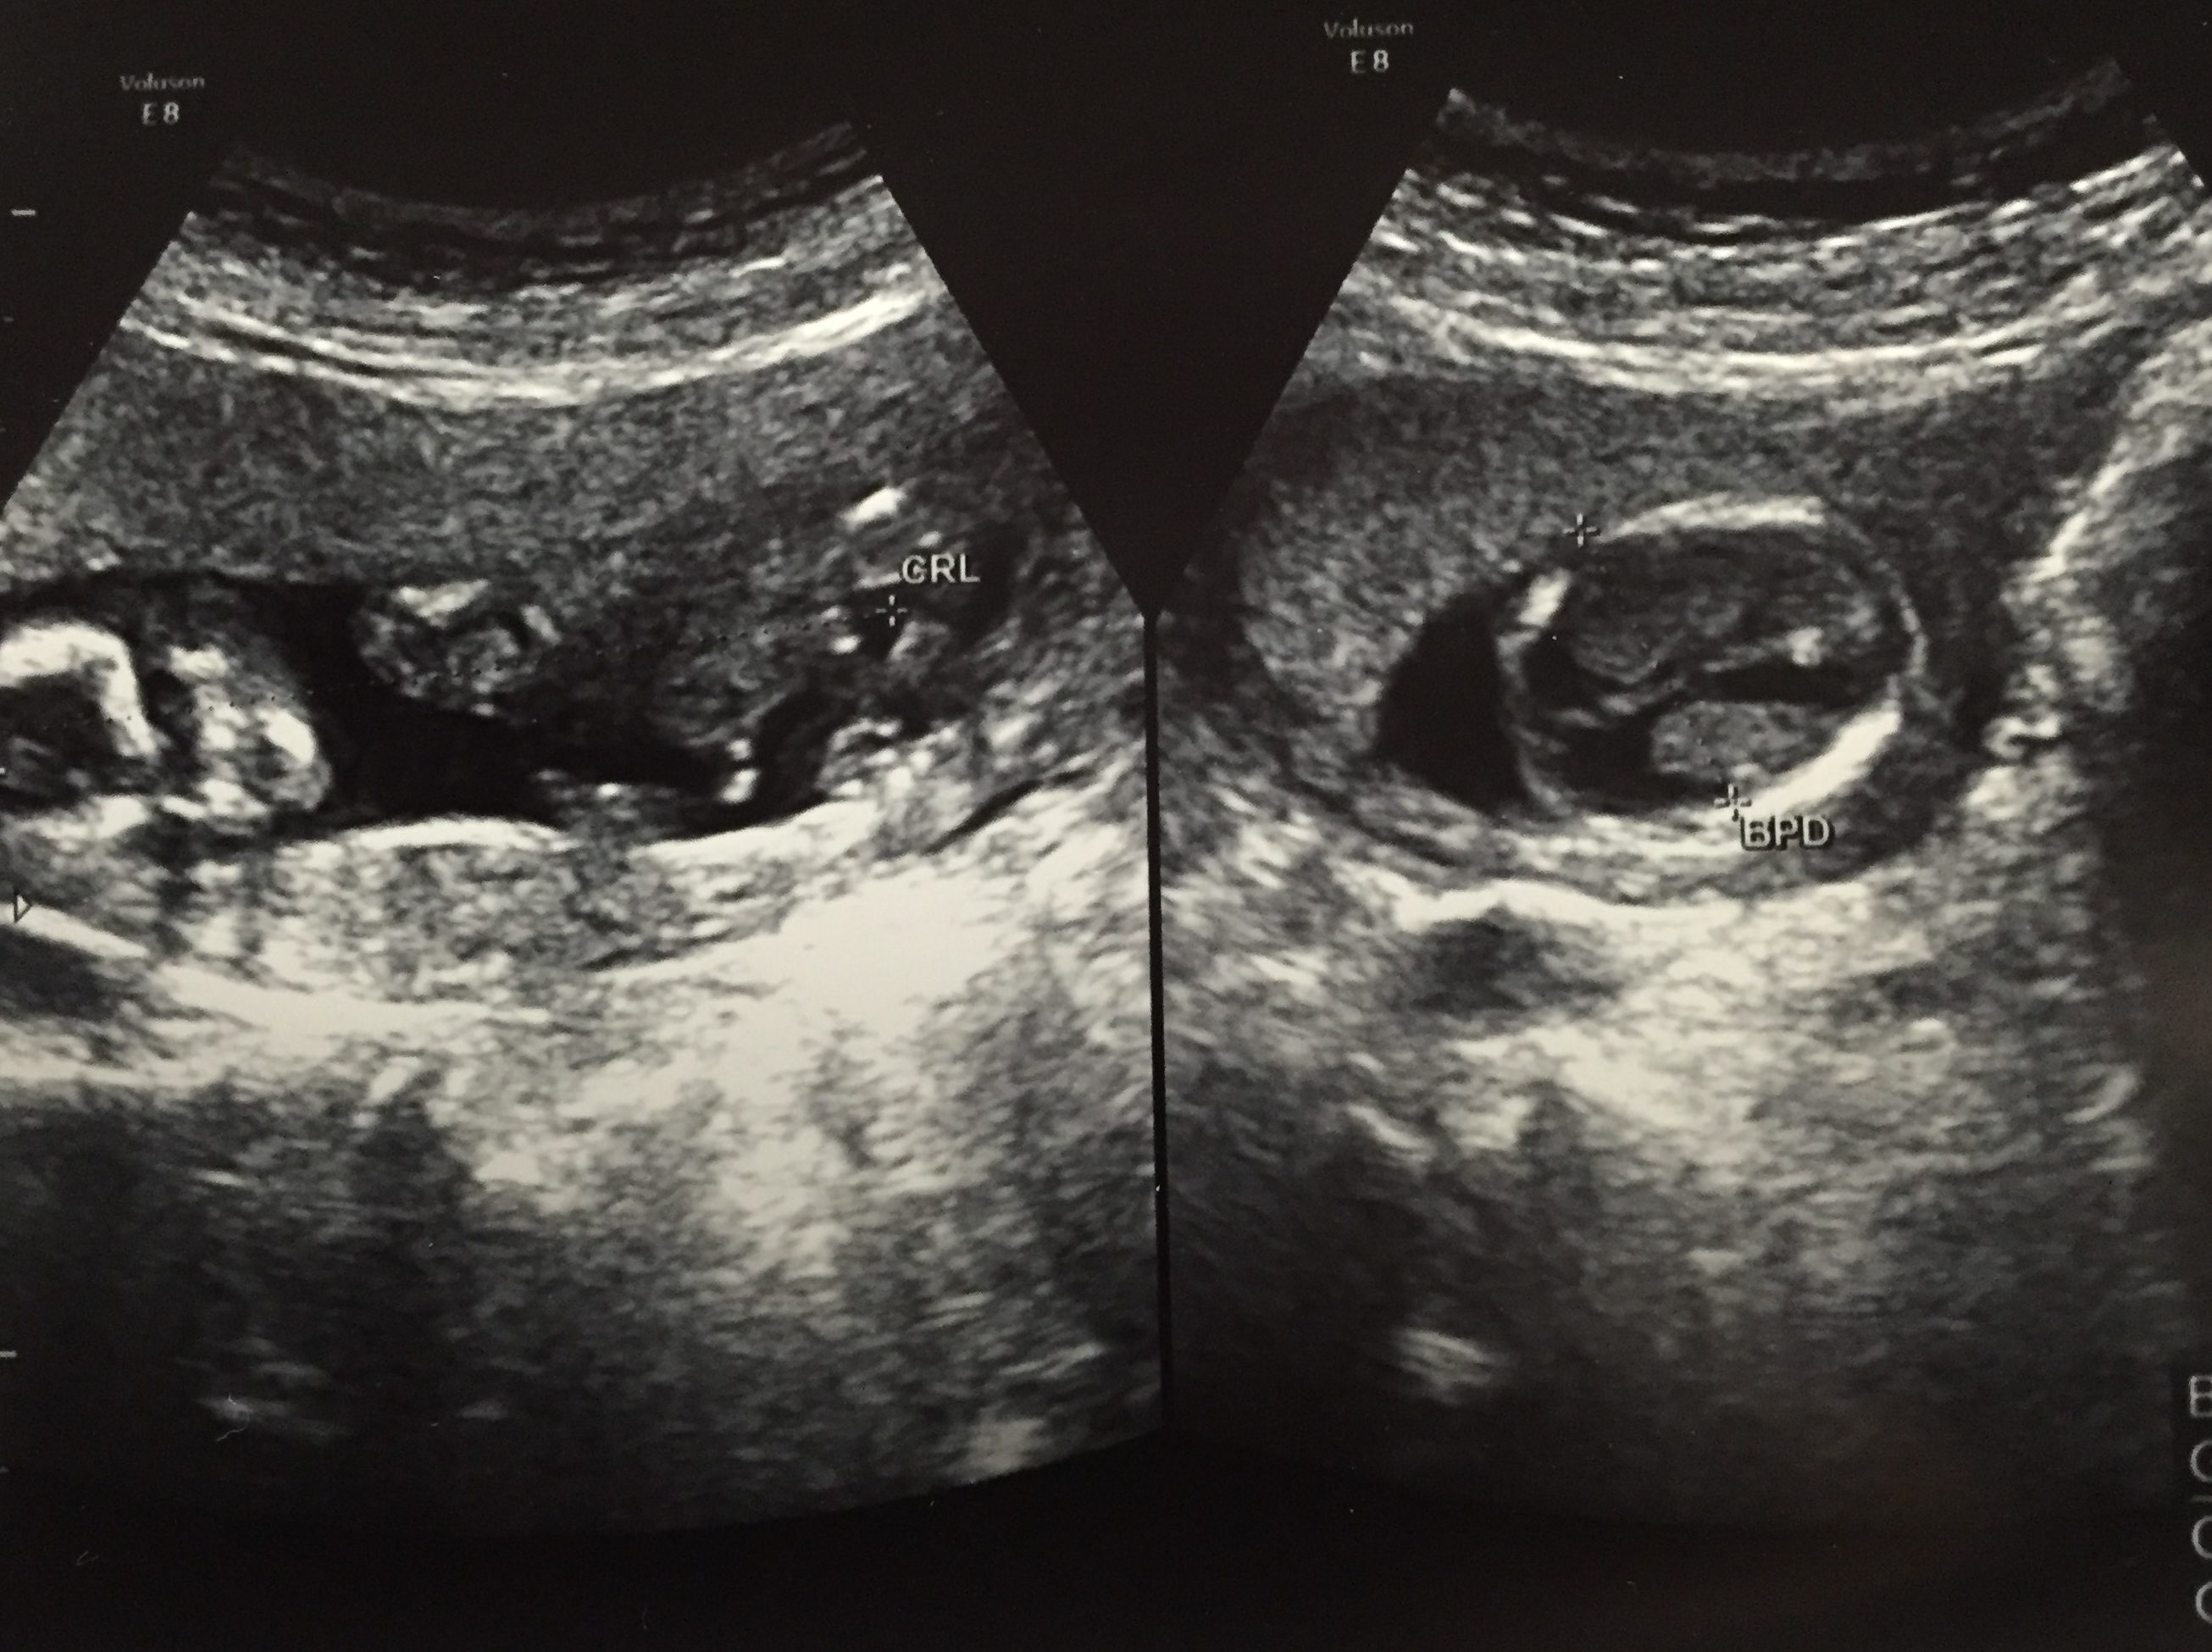

妊娠14週 3 6日 のエコー写真 体験談

妊娠14週 0 2日 のエコー写真 体験談

妊娠14週 赤ちゃんのエコー写真 超音波写真まとめ たまひよ

妊婦健診 14週 エコー写真あり にくまん Note

妊娠14週1日 14w1d の超音波 エコー 写真

妊娠14週目エコー写真 胎児の大きさ お腹の張りは大丈夫 妊娠初期 All About

妊娠14週 赤ちゃんのエコー写真 超音波写真まとめ たまひよ

妊娠14週 赤ちゃんのエコー写真 超音波写真まとめ たまひよ

育児日記 新米パパの記録 妊娠14週目の超音波写真

妊娠14週 赤ちゃんのエコー写真 超音波写真まとめ たまひよ

妊娠14週目 14w0d 6d のエコー写真とエピソード 妊娠4ヶ月 Cozre コズレ 子育てマガジン

妊娠14週 赤ちゃんのエコー写真 超音波写真まとめ たまひよ

妊娠14週 エコー写真 脳が透けて見える 初めての妊娠 赤ちゃんはリアルタイムで成長している ブログ

妊娠14週目エコー写真 胎児の大きさ お腹の張りは大丈夫 妊娠初期 All About